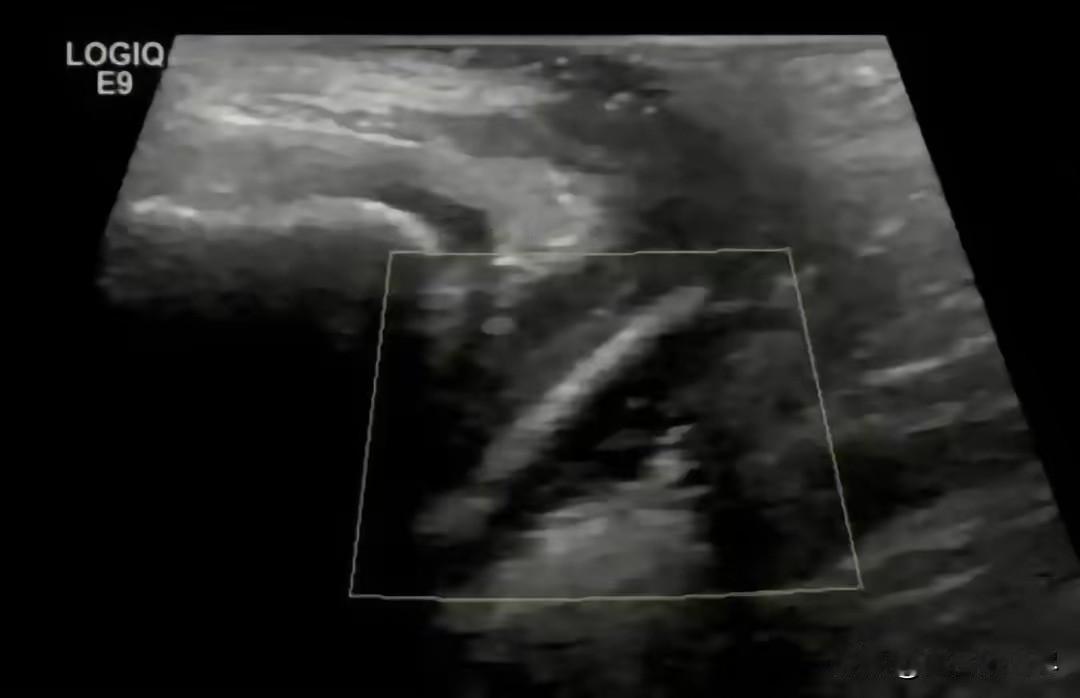

抵达深圳的医院后,医生详细了解了孩子的症状表现,以及前期的处理方式,立刻安排了针对性的检查。结合孩子反复阴道炎的特殊情况,医生排除了普通炎症的可能,怀疑是私处存在异物,才引发了持续性的炎症反应,随即展开深入检查。

经过专业的医学检查,医生最终确认了病因,孩子阴道内确实存在异物,这也是炎症久治不愈的核心原因。随后医生通过专业操作,小心翼翼地从孩子体内取出异物,取出后发现,这是一支完整的试用装精华液,并非医疗用品。